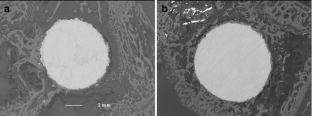

Fig. 1

Fig. 2